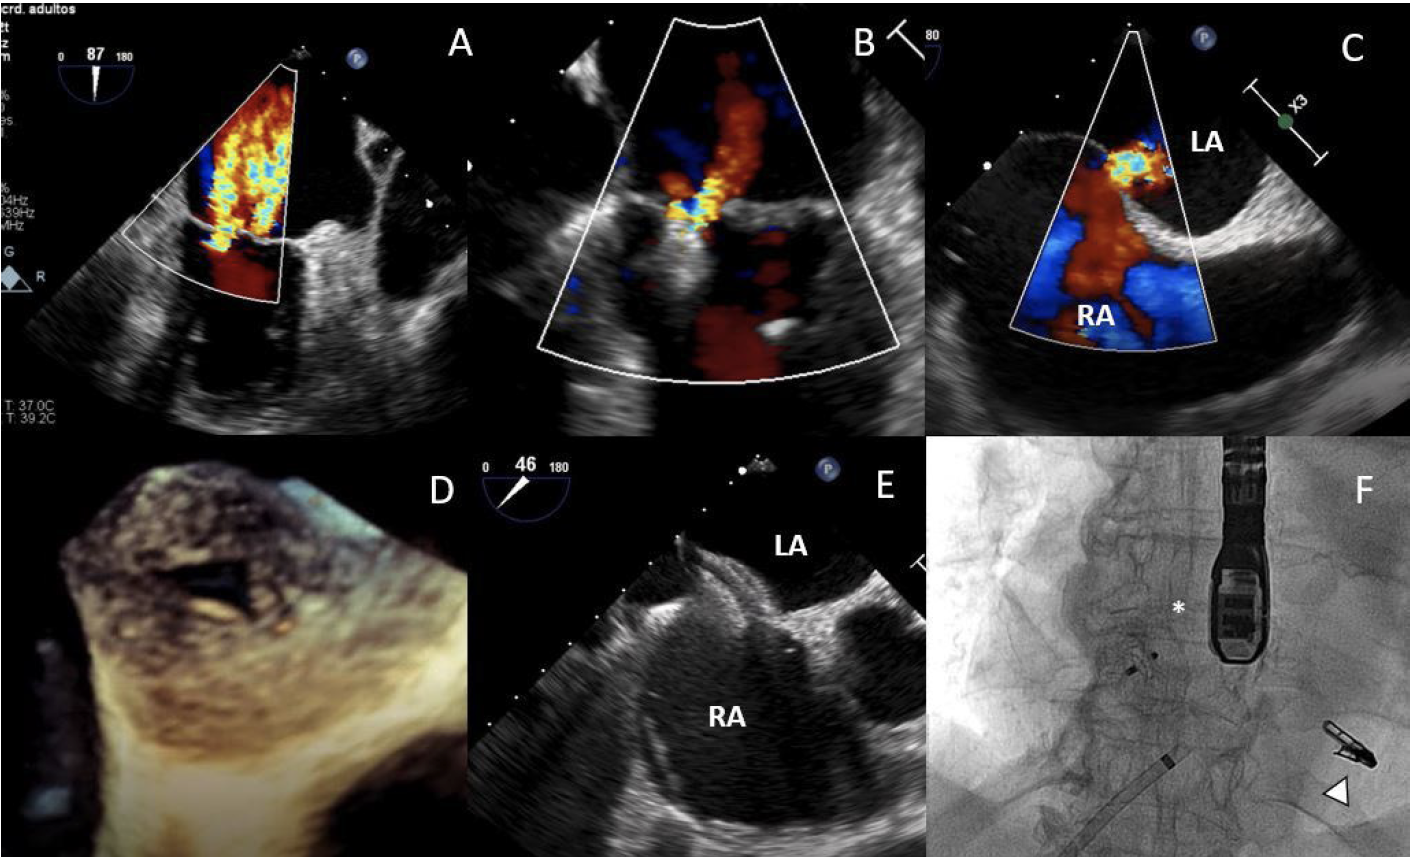

An 80-year-old female patient with atrial fibrillation and chronic kidney disease was admitted for heart failure. Severe functional mitral regurgitation (MR) and torrential tricuspid regurgitation (TR) (Figures 1A, 2A; Video Series) were detected on the echocardiogram.

She was rejected for a high-risk surgery and was referred for MitraClip repair. One XTR clip was implanted between A3-P3 leaflets with mild residual MR (Figure 1B; Video Series). After the procedure, the patient suffered abrupt oxygen desaturation. Echocardiogram revealed a right-to-left shunt through an iatrogenic atrial septal defect (Figures 1C, 1D). It was successfully closed with a 12-mm Amplatzer septal occluder (Figures 1E, 1F; Video Series) showing an immediate hemodynamic improvement.